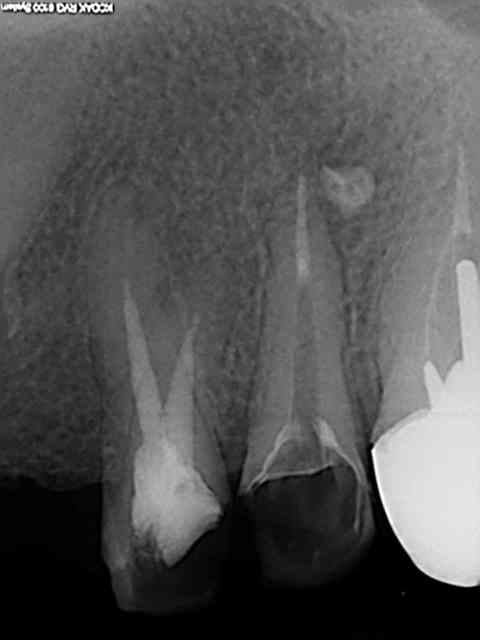

J'utilise le système heroshaper+digue+hypo+condensation

Mac Spadden(thermomécanique)

J'ai posté des radios biopulpectomies et retraitements

canalaires précédemment.

L'obturation 3D est indispensable pour un traitement hermétique.Mon associé utilise le système protaper et

effectivement cela élargit plus.Sur ces 7 dernières années

j'obtiens de bons résultats;mon avis le système heroshaper

casse moins mais n'hésite pas à jeter un heroshaper

même si non déspiralé ;si il a travaillé un peu en force

ou si la morphologie canalaire est un peu compliquée ou courbe;on fait un peu un usage unique pour éviter tout

problème plus tard!(quelque soit le système)on récapitule

avec un instrument à mains;pour une bonne herméticité

le système Mac spadden est le plus efficace ,utlisé par des endos exclusifs,et le moins cher (un cone de gutta est suffisant)Ma séquence classique instrument à main N10

héroshaper N20 6%/4% N25 4% N30 4% MAC SPADDEN un cone de gutta/ciment sealite régular

J'ai reposté quelques radios de biopulpectomies

RTE dans un précédent post...